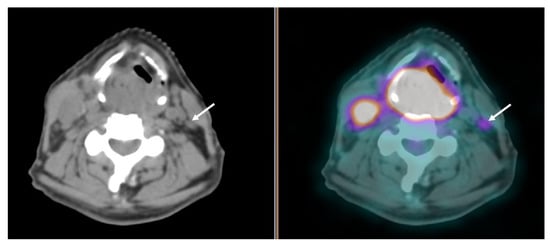

- the high rate of cystic/necrotic neck metastasis with a typical low 18F-FDG uptake [68];